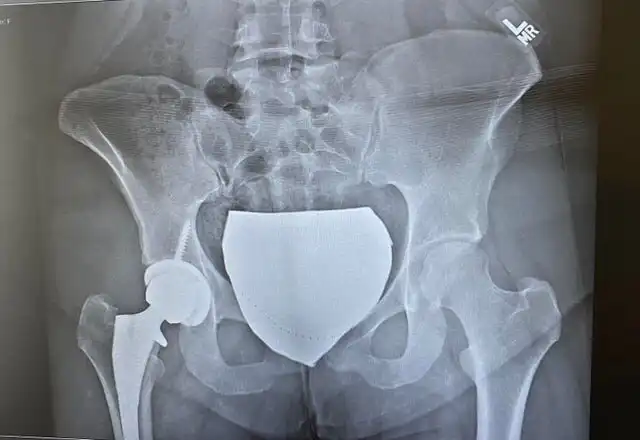

Мне 24 года, и я теперь чувствую, когда пойдет дождь